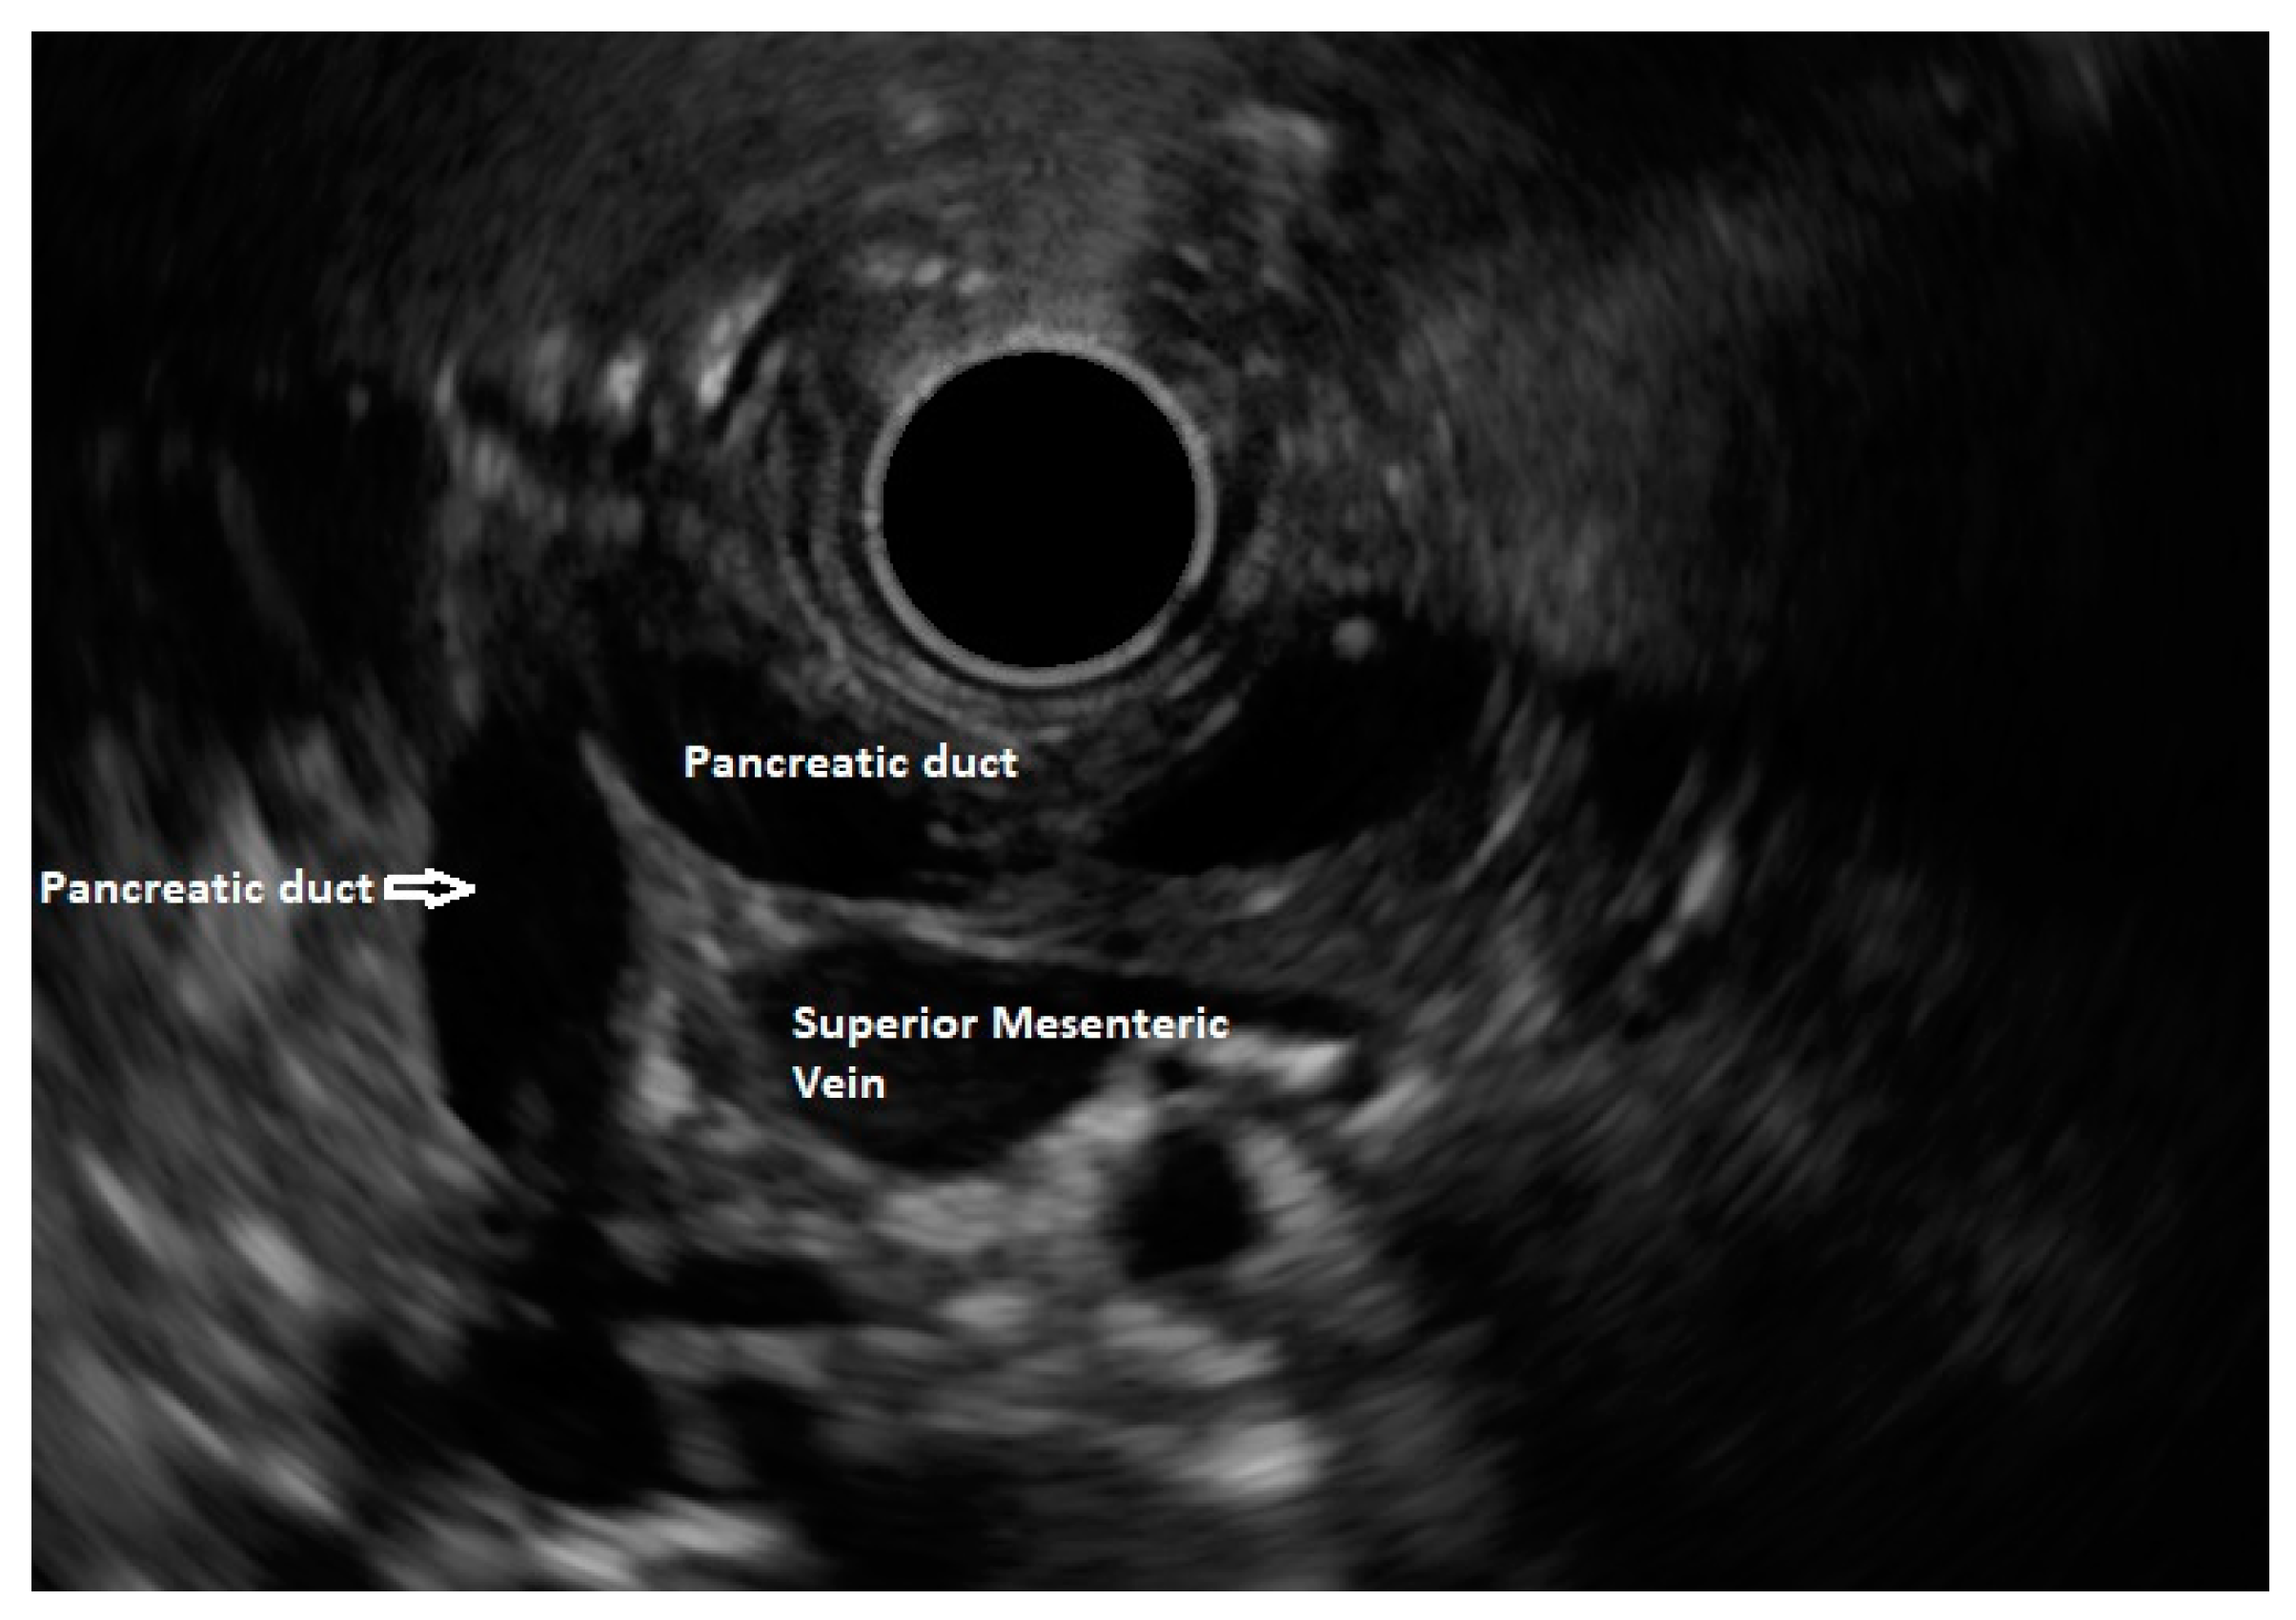

In routine endosonographic examinations, all parts of the pancreas are comprehensively examined when seen from three stations: the apex of the duodenal bulb, papilla, and distal to the papilla. Among these, the best position is the apex of the duodenal bulb as it brings the major portion of the head of the pancreas, distal common bile duct, and portal vein in the same frame. For positioning, the EUS scope is advanced along the greater curvature of the stomach and when pylorus is visible, the tip of the scope is negotiated through it, followed by air insufflation of the duodenal bulb. This is followed by gentle downward deflection of the tip of the scope, making the duodenal bulb visible. Doppler imaging helps differentiating bile duct from the arteries (the hepatic artery and gastroduodenal artery) and the portal vein. At this point, the endosonologist gets the view of the distal CBD, pancreatic duct, and portal vein in a single frame in which one structure appears to lie on top of the other, and this is called the stack sign (Figure 1). Absence of the stack sign suggests the possibility of pancreas divisum (Figure 2). As these structures do not lie in the same plane, various maneuvers like clockwise and counter-clockwise rotation and right and left torque are required for a detailed examination of these structures [12]. Although this sign is conventionally described in radial EUS, linear EUS can also detect similar anatomical configuration, although there are some subtle differences in linear EUS. In linear EUS, usually, the “stack” consists of the distal CBD and pancreatic duct, which are seen on a parallel axis (the portal vein is not seen). However, the superior mesenteric vein (SMV) or artery (SMA) can be seen on linear EUS on a different axis, once a clockwise rotation is performed, and the origin of the portal vein from the SMV can also be easily demonstrated (Figure 3) [27].

Figure 3.

Stack sign on linear EUS.